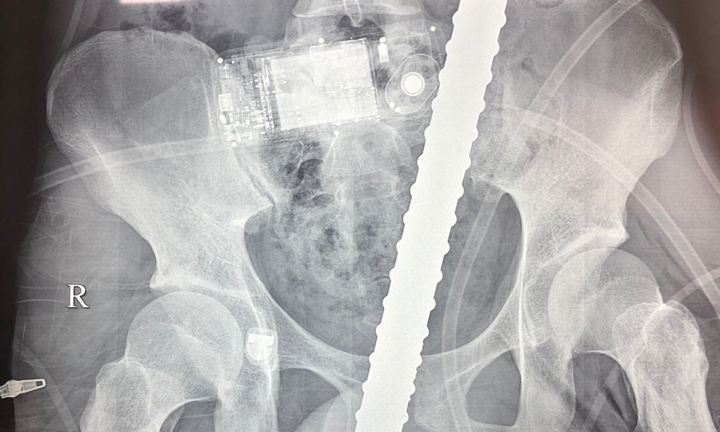

Bệnh nhân nhập viện trong tình trạng chảy máu nhiều, 2 thanh sắt đâm xuyên đùi, bụng ngực.